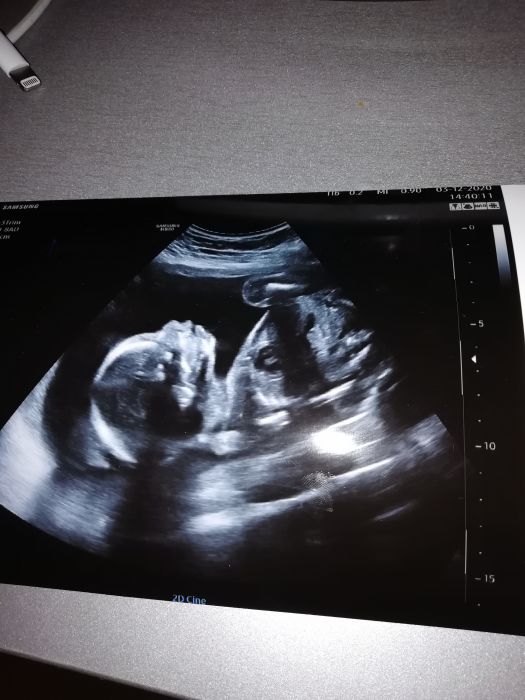

jinak začalo me tvrdnout břicho tak zas začínám brát magnesko ráno a večer...už se těším na ten velkej druhej ultrazvuk mám ho až 15...to budu 22 TT...jinak Vánoce

AHOJ maminky. Přidávám se k Vám :) máme terminek někdy 22. 4 ale jelikož půjdu na plánovaný císař tak to bude urcote o nějaky ten týden dřív. Teď jsem 21tt a už máme za sebou velký ultrazvuk. Čekáme 3ti dítko a bude to holčička :) doma už mám jednu 6ti letou a skoro 4 leteho syna a už se moc těšíme až nás bude víc :)

.ty ultrazvuku jsou boží prostě jak jde vidět úplně všechno